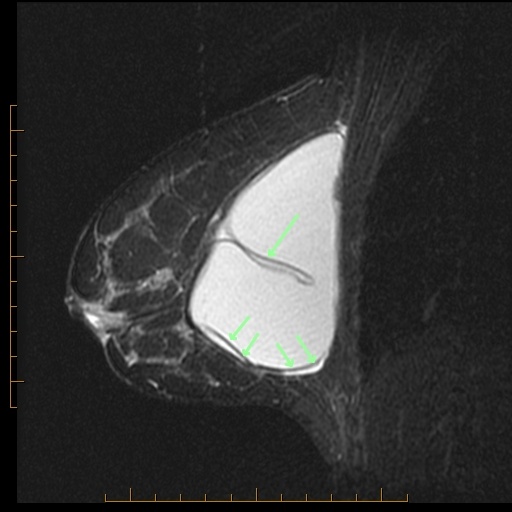

Name all the signs you can see on these sagittal T2 images from each breast. Next, name all the signs you can think of that signify MRI evidence of intracapsular implant rupture. Then be sure to scroll below the images to check your findings against mine.

Right breast (left) is collapsed; loop or lariat sign (two arrows); fall away sign (four arrows) when implant falls away from biological fibrous shell.

Other signs include: Linguine sign (the classic intracapsular rupture sign), and the bubble-mixing sign, both not present in this case. All represent intracapsular implant rupture.